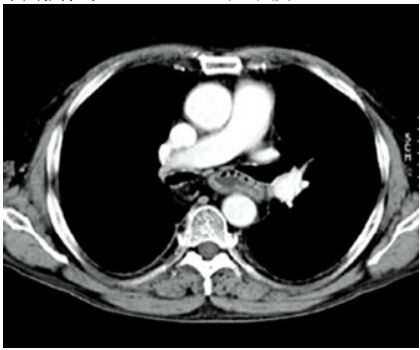

38.男性患者突然左胸痛,未施打顯影劑的胸腔電腦斷層在左肺旁發現異常(如下圖所示),最適當的診斷為 何?

(A)氣胸(pneumothorax) (B)血胸(hemothorax) (C)乳糜胸(chylothorax) (D)連枷胸(flail chest)